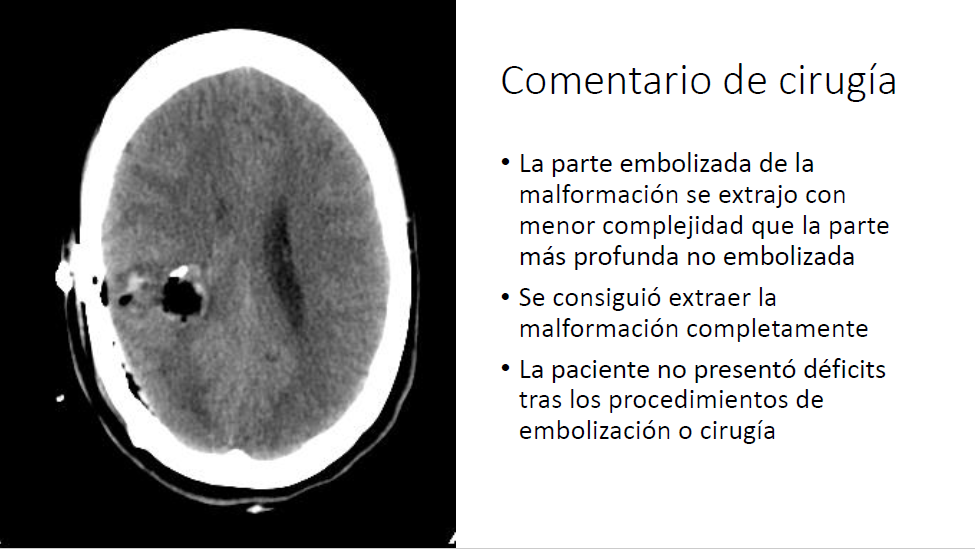

Tratamiento combinado de malformación arteriovenosa con sangrado reciente